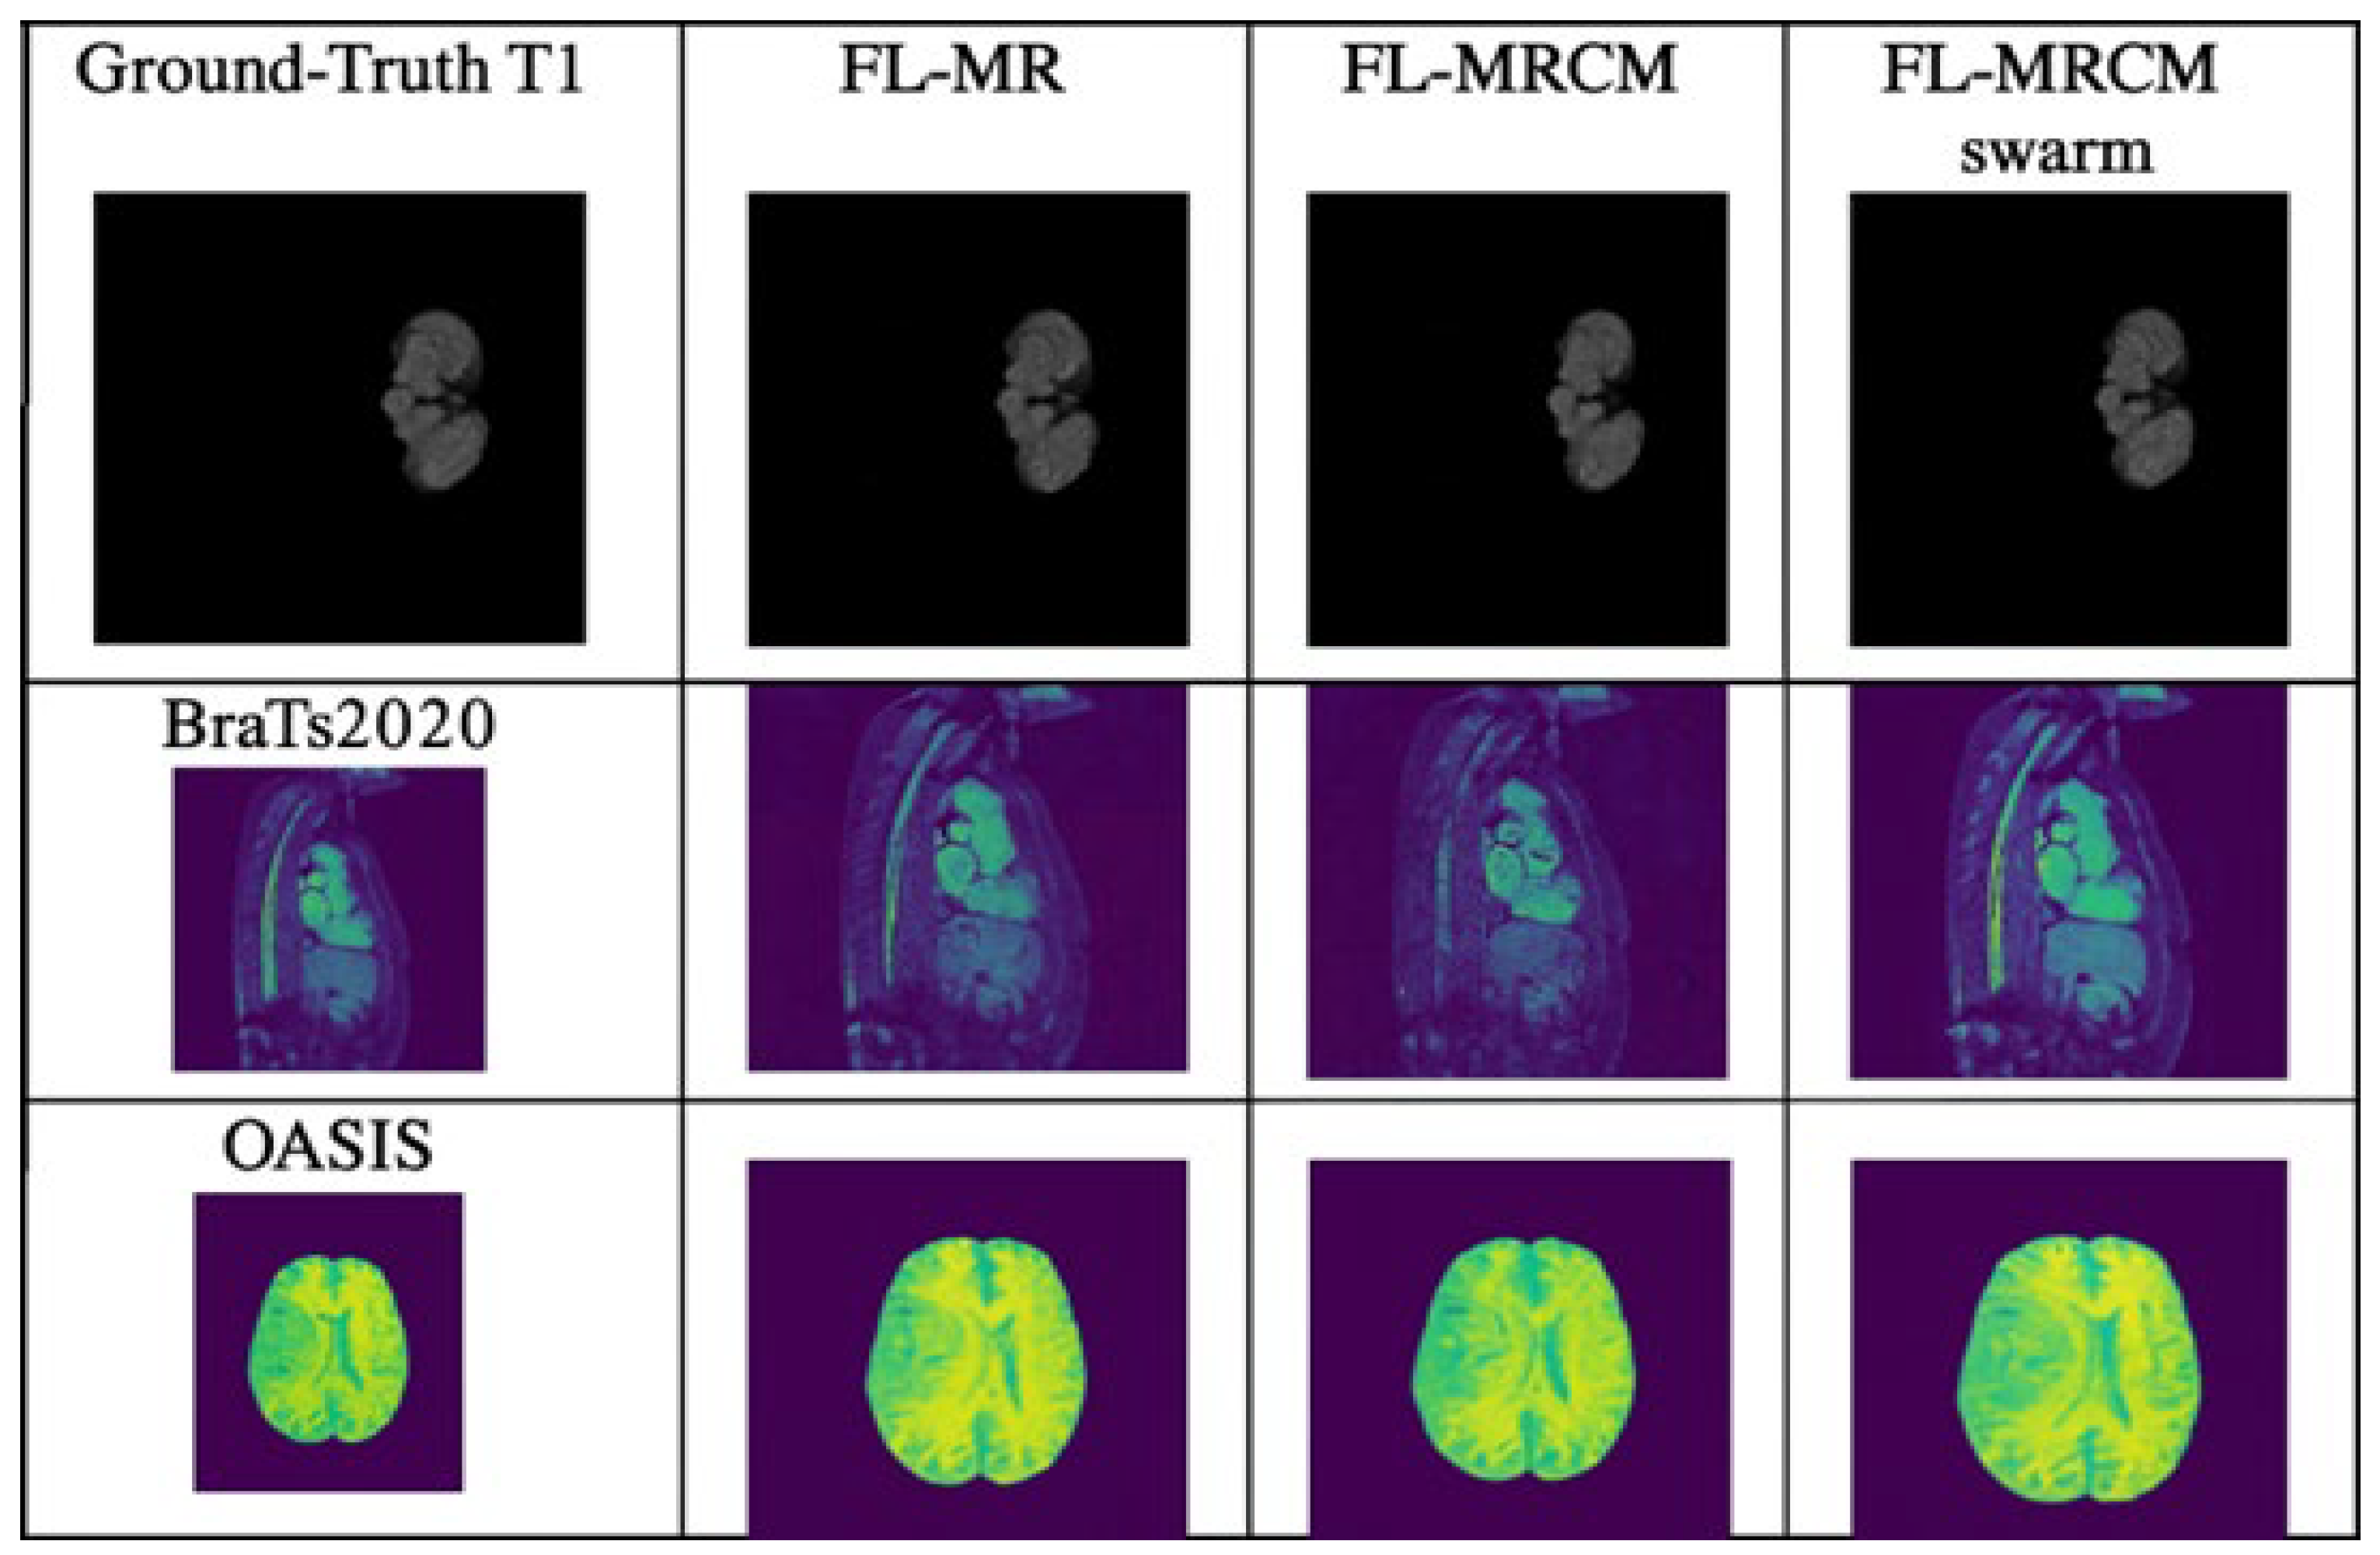

The research carried out and the experiments conducted exhibit the efficacy of the proposed methodology. The experiments were conducted using two different scenarios. In scenario 1, the effectiveness of the proposed technique was analyzed by improving the applicability and portability of the trained models and thus improving its usage compared against the previously used methodologies. The performance of the trained model is determined after subjecting it to a dataset which is not used directly during training process. Incidentally, a dataset emulates an institution, and the datasets from other sites are chosen for training purposes which are commonly seen in clinical practices. The user institutions do not have access to complete and fully sampled image databases for all training purposes in scenario 2 as shown in Figure 9. The proposed methodology is evaluated by first training the dataset which is made available from all the institutions to exhibit the benefits of collaboration of the datasets via the federated learning technique.

Detailed ablation studies were conducted to analyze the efficiency of the proposed methodology. Here, a trained model was obtained from one of the sites (institutions) and evaluated against data from another institution. The performance metrics obtained after executing the FL algorithms are tabulated in Table 5. It is clear from Table 5 that the proposed FL-SwarmGAN MRCM outperforms, exhibiting better collaborations and generalizability. It clearly improves the reconstruction image quality in every dataset as shown in Figure 11 and Figure 12. The qualitative reconstruction comparisons for cross-site scenarios (B-B, B-F, and B-O) are presented in Figure 11. This figure illustrates the visual differences between FL-MRCM and FL-MRCM-Swarm across varying institutional configurations. The red boxes highlight the regions of interest used to visually assess reconstruction differences between the methods.